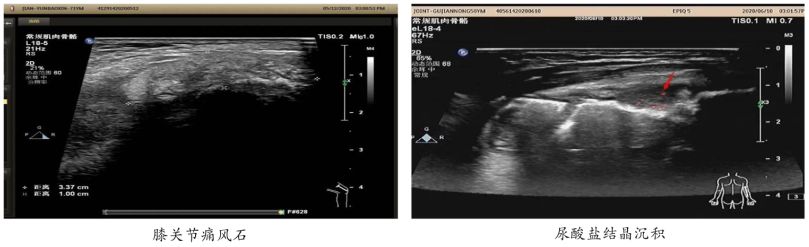

肌骨超声 精准检测

对尿酸结晶盐堆积程度、数量及大小、关节腐蚀程度和代谢情况做出精准检测。